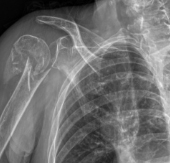

What is Shoulder Replacement Surgery?

Shoulder Replacement After Fracture

In the case of a complex fracture which has caused significant joint damage, shoulder replacement may be recommended to restore stability, reduce pain, and improve shoulder function.